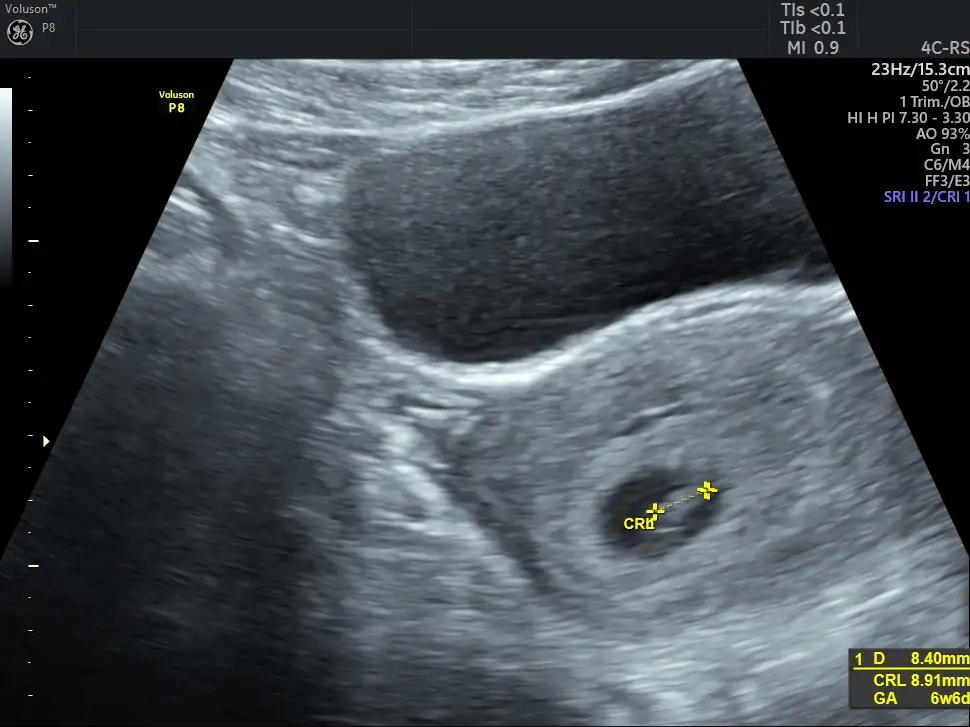

• 7E8AD59B-2C57-4E1A-9D39-3F01A9A66057.webp

7E8AD59B-2C57-4E1A-9D39-3F01A9A66057.webp

36,1 KB · Görüntüleme: 60